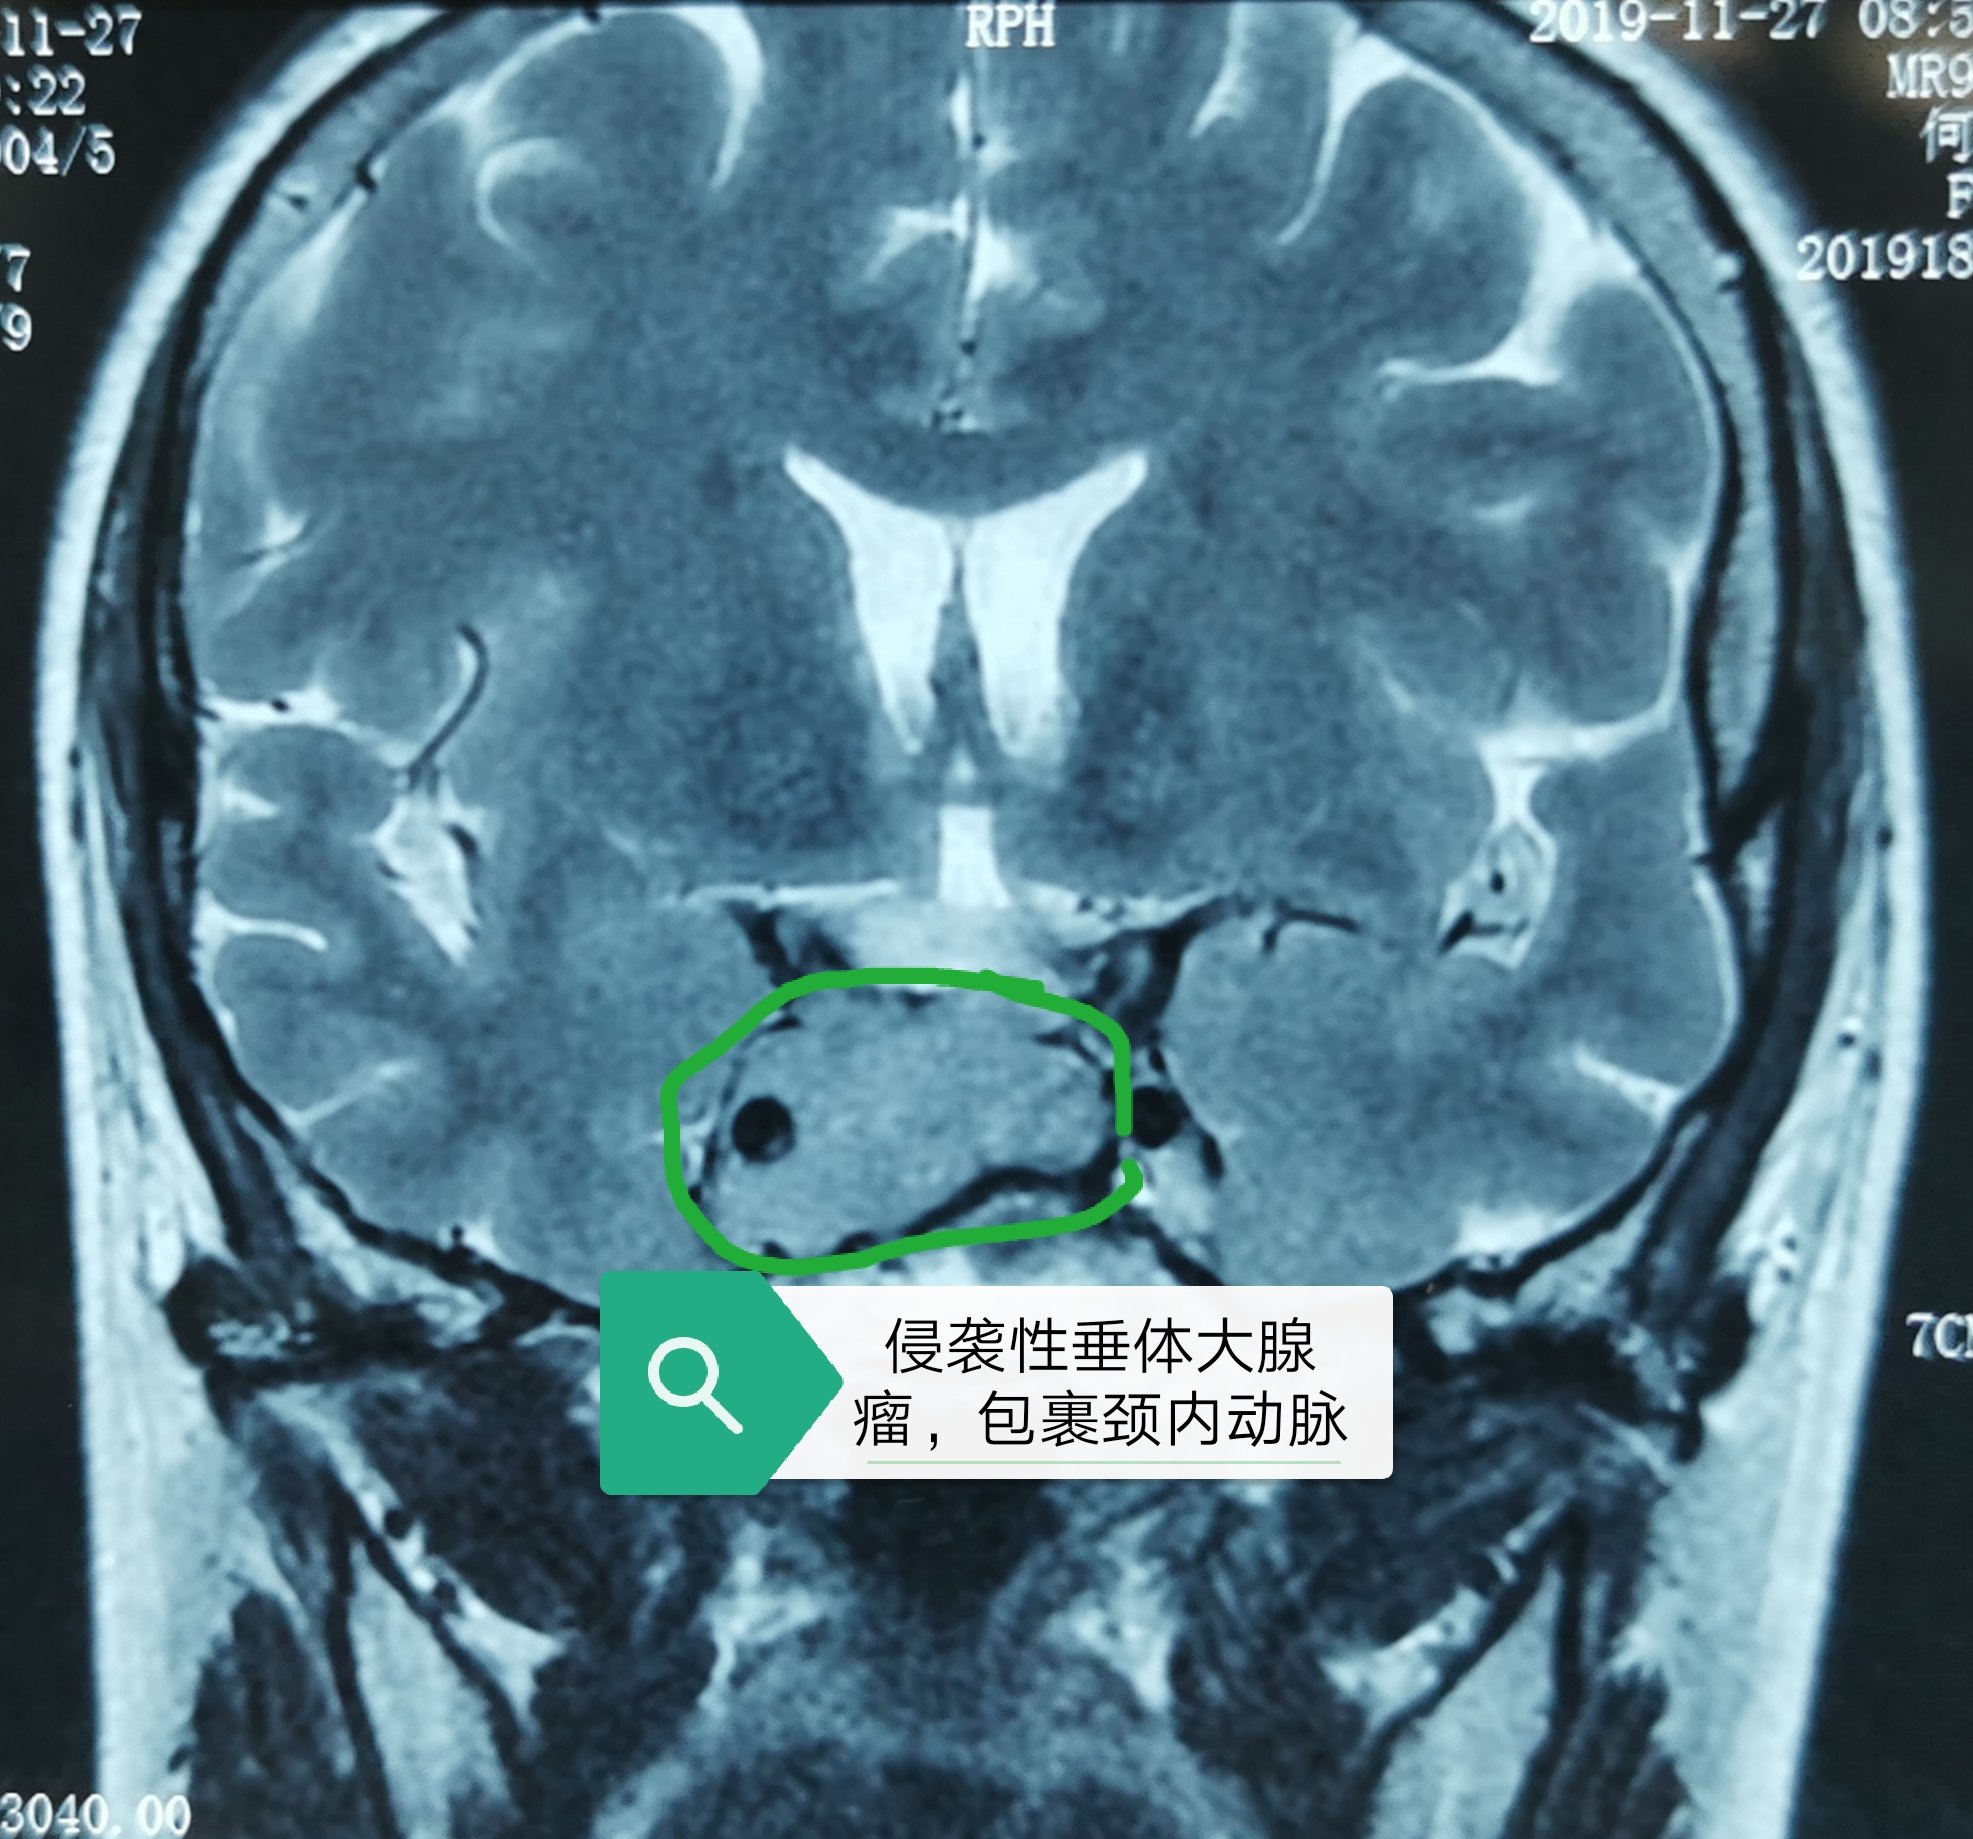

神经内镜下顺利切除二台侵袭性垂体大腺瘤 - 好大夫在线